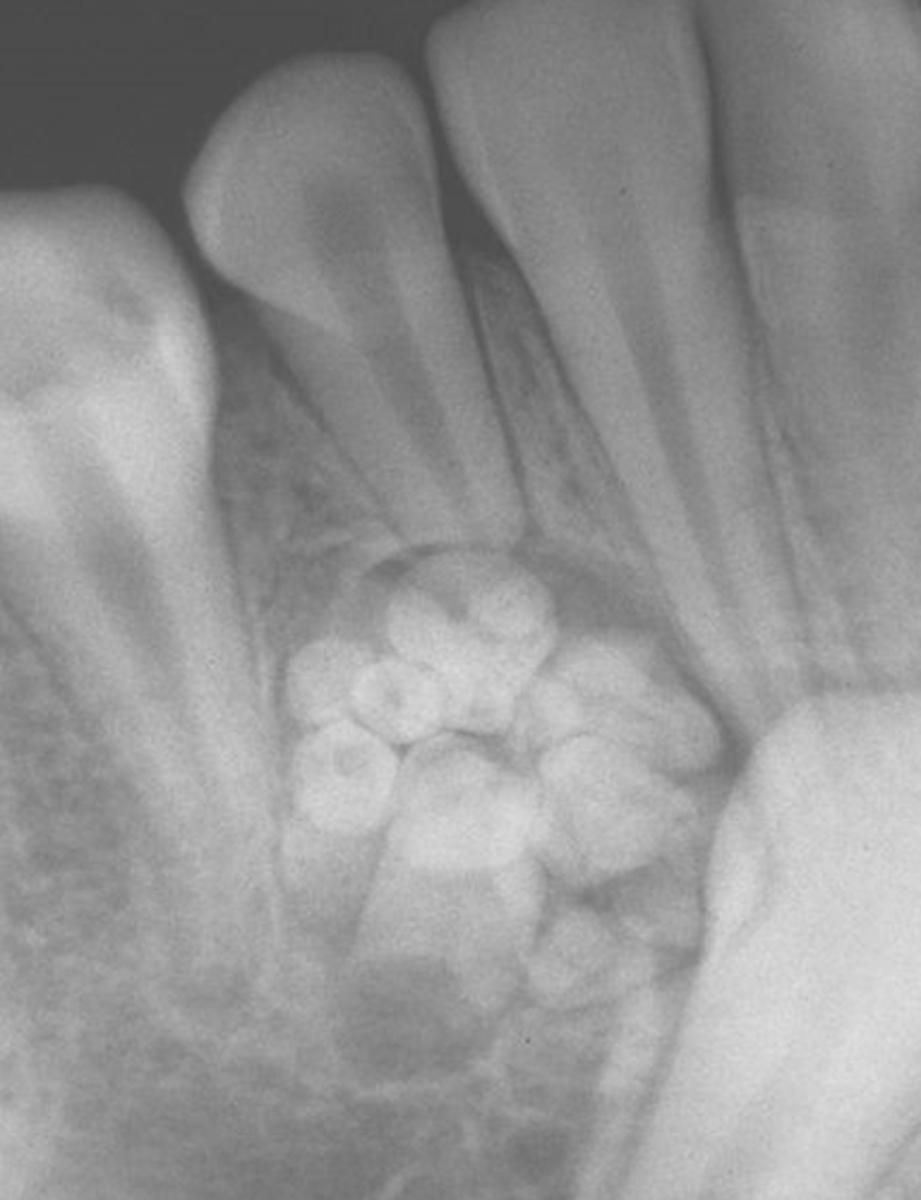

A compound odontoma resembles

small teeth

compound odontoma radiographically is

cluster of miniature teeth

Compound odontoma